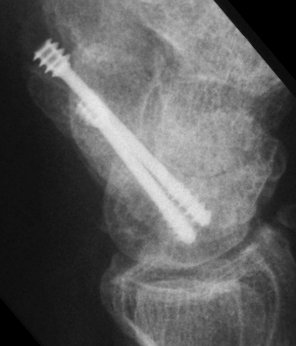

Case 8. Transscaphoid perilunate fracture dislocation...

Two screws put in dorsally, LT ligament reinforced with a strip of extensor retinaculum left attached to the triquetrium and anchored into the lunate; temporary capitolunate pin.

Click for larger image